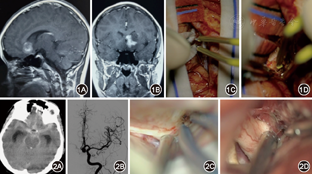

(1)手术过程和评估方法:按照常规手术入路,前循环动脉瘤采用额底外侧入路,翼点入路,小脑后下动脉动脉瘤采用远外侧入路。近中线幕上病变采用经前、后纵裂入路,桥小脑角肿瘤采用枕下乙状窦后入路,后颅窝肿瘤采用枕下后正中入路和旁正中入路,岩斜区病变采取颞下入路,所有手术术中使用蔡司Pentero显微镜,术者座位手术,配合托手架、口控设备,根据需要术中配合吲哚菁绿荧光造影、多模态神经导航、神经电生理监测、术中B超技术。病变残留判断:动脉瘤和动静脉畸形依据术后CTA或DSA检查,肿瘤病变依据术后MRI判断是否病变残留,周围组织挫伤判断依据术后当天CT检查,有卒中病史依据改良RANKIN量表(mRS)评分,无卒中病史依据Karnofsky功能状态(KPS)评分,分别在入院和出院时进行神经功能评估。(2)无牵开器动态牵拉手术技术要点:右利手医生,右手持双极和显微器械,左手持吸引器,吸引器不仅起吸引作用,还可以辅助进行细微牵拉,探查及剥离界面,吸引器需要保持适度的湿润,防止进出术区粘连脑组织,如图1所示,可以配合棉片,扩大支撑范围。术中通过合适的吸引器配合双极镊子和棉片轻柔地沿蛛网膜自然界面牵开脑组织,快速有效的释放脑脊液可以获得足够的手术空间,如在常见的颅内动脉瘤手术过程中通过双极电凝镊配合棉片牵开脑组织方便吸引器吸除脑脊液,吸引器配合又能保证双极电凝镊的操作空间,如图2所示,通过额底外侧入路快速打开视交叉池甚至终板,可以有效的释放脑脊液降低颅内压。在熟悉掌握了这一技术后,习惯性的交替使用吸引器和双极镊子可以替代牵开器,避免牵开器持续牵拉局部脑组织导致的脑挫伤。在没有持续使用牵开器牵拉脑组织手术过程中,如图3A所示需要左手的吸引器保持相对的稳定位置作为视觉参考点,这样能避免左手器械反复进出术野,保持左手的牵开功能,保证之前操作获得的手术界面和空间。右手一般采取盲操作进行器械交换,并且通过右手配合显微镜附带的口控功能,可以进行单手显微镜的移动,如图3B所示口控装置可以完成上、下、左、右的移动,对于较大的放大倍数下操作尤为重要,通过口控进行四个方向细微的移动。即使在需要改变显微镜角度和工作距离情况下,如图3A所示,口控开关作为辅助支点,也能达到右手单手控制显微镜任意角度和位置。包括配套的多功能手术坐椅综合了前臂稳定系统和双脚控制系统如图3C所示,最大限度地减少双手离开手术界面,能有效地减少了器械反复出入术区地次数,避免重复地动作和操作的副损伤,这一点在无牵开器动态牵拉手术中至关重要。(3)手术体位需要注意以下几点:患者头部应该高于心脏水平位置大约20 cm;头部倾斜避免颈部受压,这样有利于良好的静脉回流;头部摆位应该考虑尽可能利用重力作用,使脑组织自如下垂,将减少术中脑组织的牵拉,扩大观察范围和手术空间[3],如翼点入路头部下垂30°,使额叶依靠重力作用远离前颅窝底;通过病灶位于下方的侧卧位处理中线或近中线病变,如纵裂入路可以使病灶侧位于大脑镰斜下方,重力作用脑组织自然下垂减少牵拉(图4),术中有利于脑组织离开大脑镰自然下垂[4];通过座位或半座位暴露枕下小脑上或者松果体区病变。